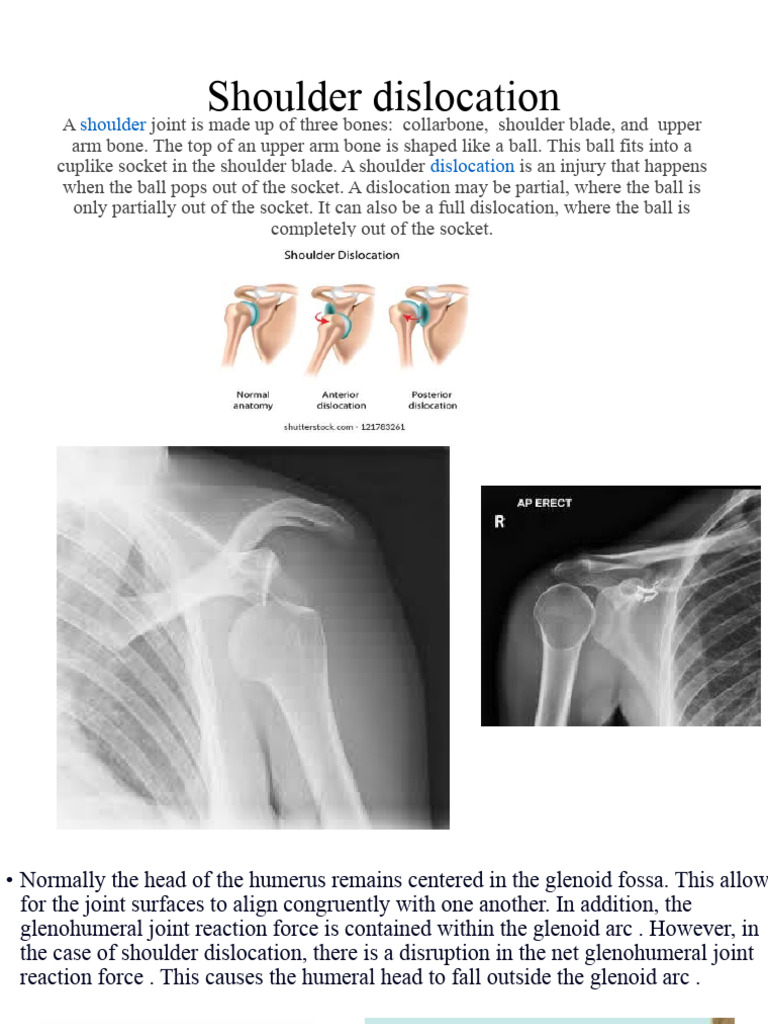

Other Terms For Shoulder Dislocation . Most commonly, the shoulder dislocates by sliding forward (anterior). what is a dislocated shoulder? dislocation of your shoulder means your upper arm bone (humerus) has come out of your shoulder joint. The shoulder joint, also known as the glenohumeral joint, is located between the upper arm bone (humerus) and. other potential causes of a shoulder dislocation include seizures and electrocutions. the term shoulder dislocation refers to the complete displacement of the humeral head from the glenoid fossa,.

what is a dislocated shoulder? dislocation of your shoulder means your upper arm bone (humerus) has come out of your shoulder joint. the term shoulder dislocation refers to the complete displacement of the humeral head from the glenoid fossa,. other potential causes of a shoulder dislocation include seizures and electrocutions. Most commonly, the shoulder dislocates by sliding forward (anterior). The shoulder joint, also known as the glenohumeral joint, is located between the upper arm bone (humerus) and.